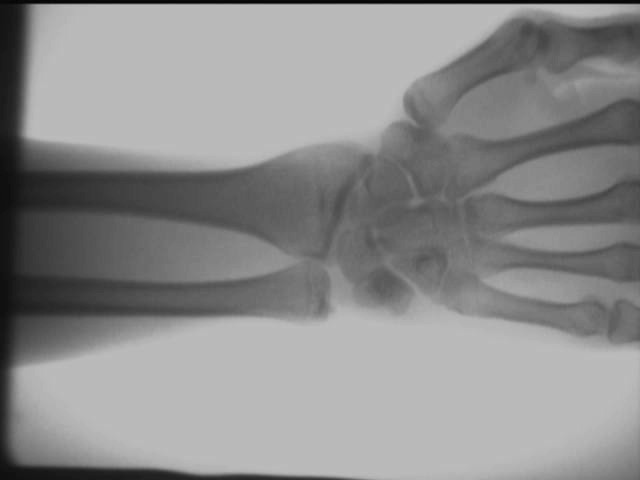

Palmperspectiefeffect

De bovenstaande testresultaten zijn ter plaatse verkregen met behulp van een AS-C200draagbaar röntgenapparaat